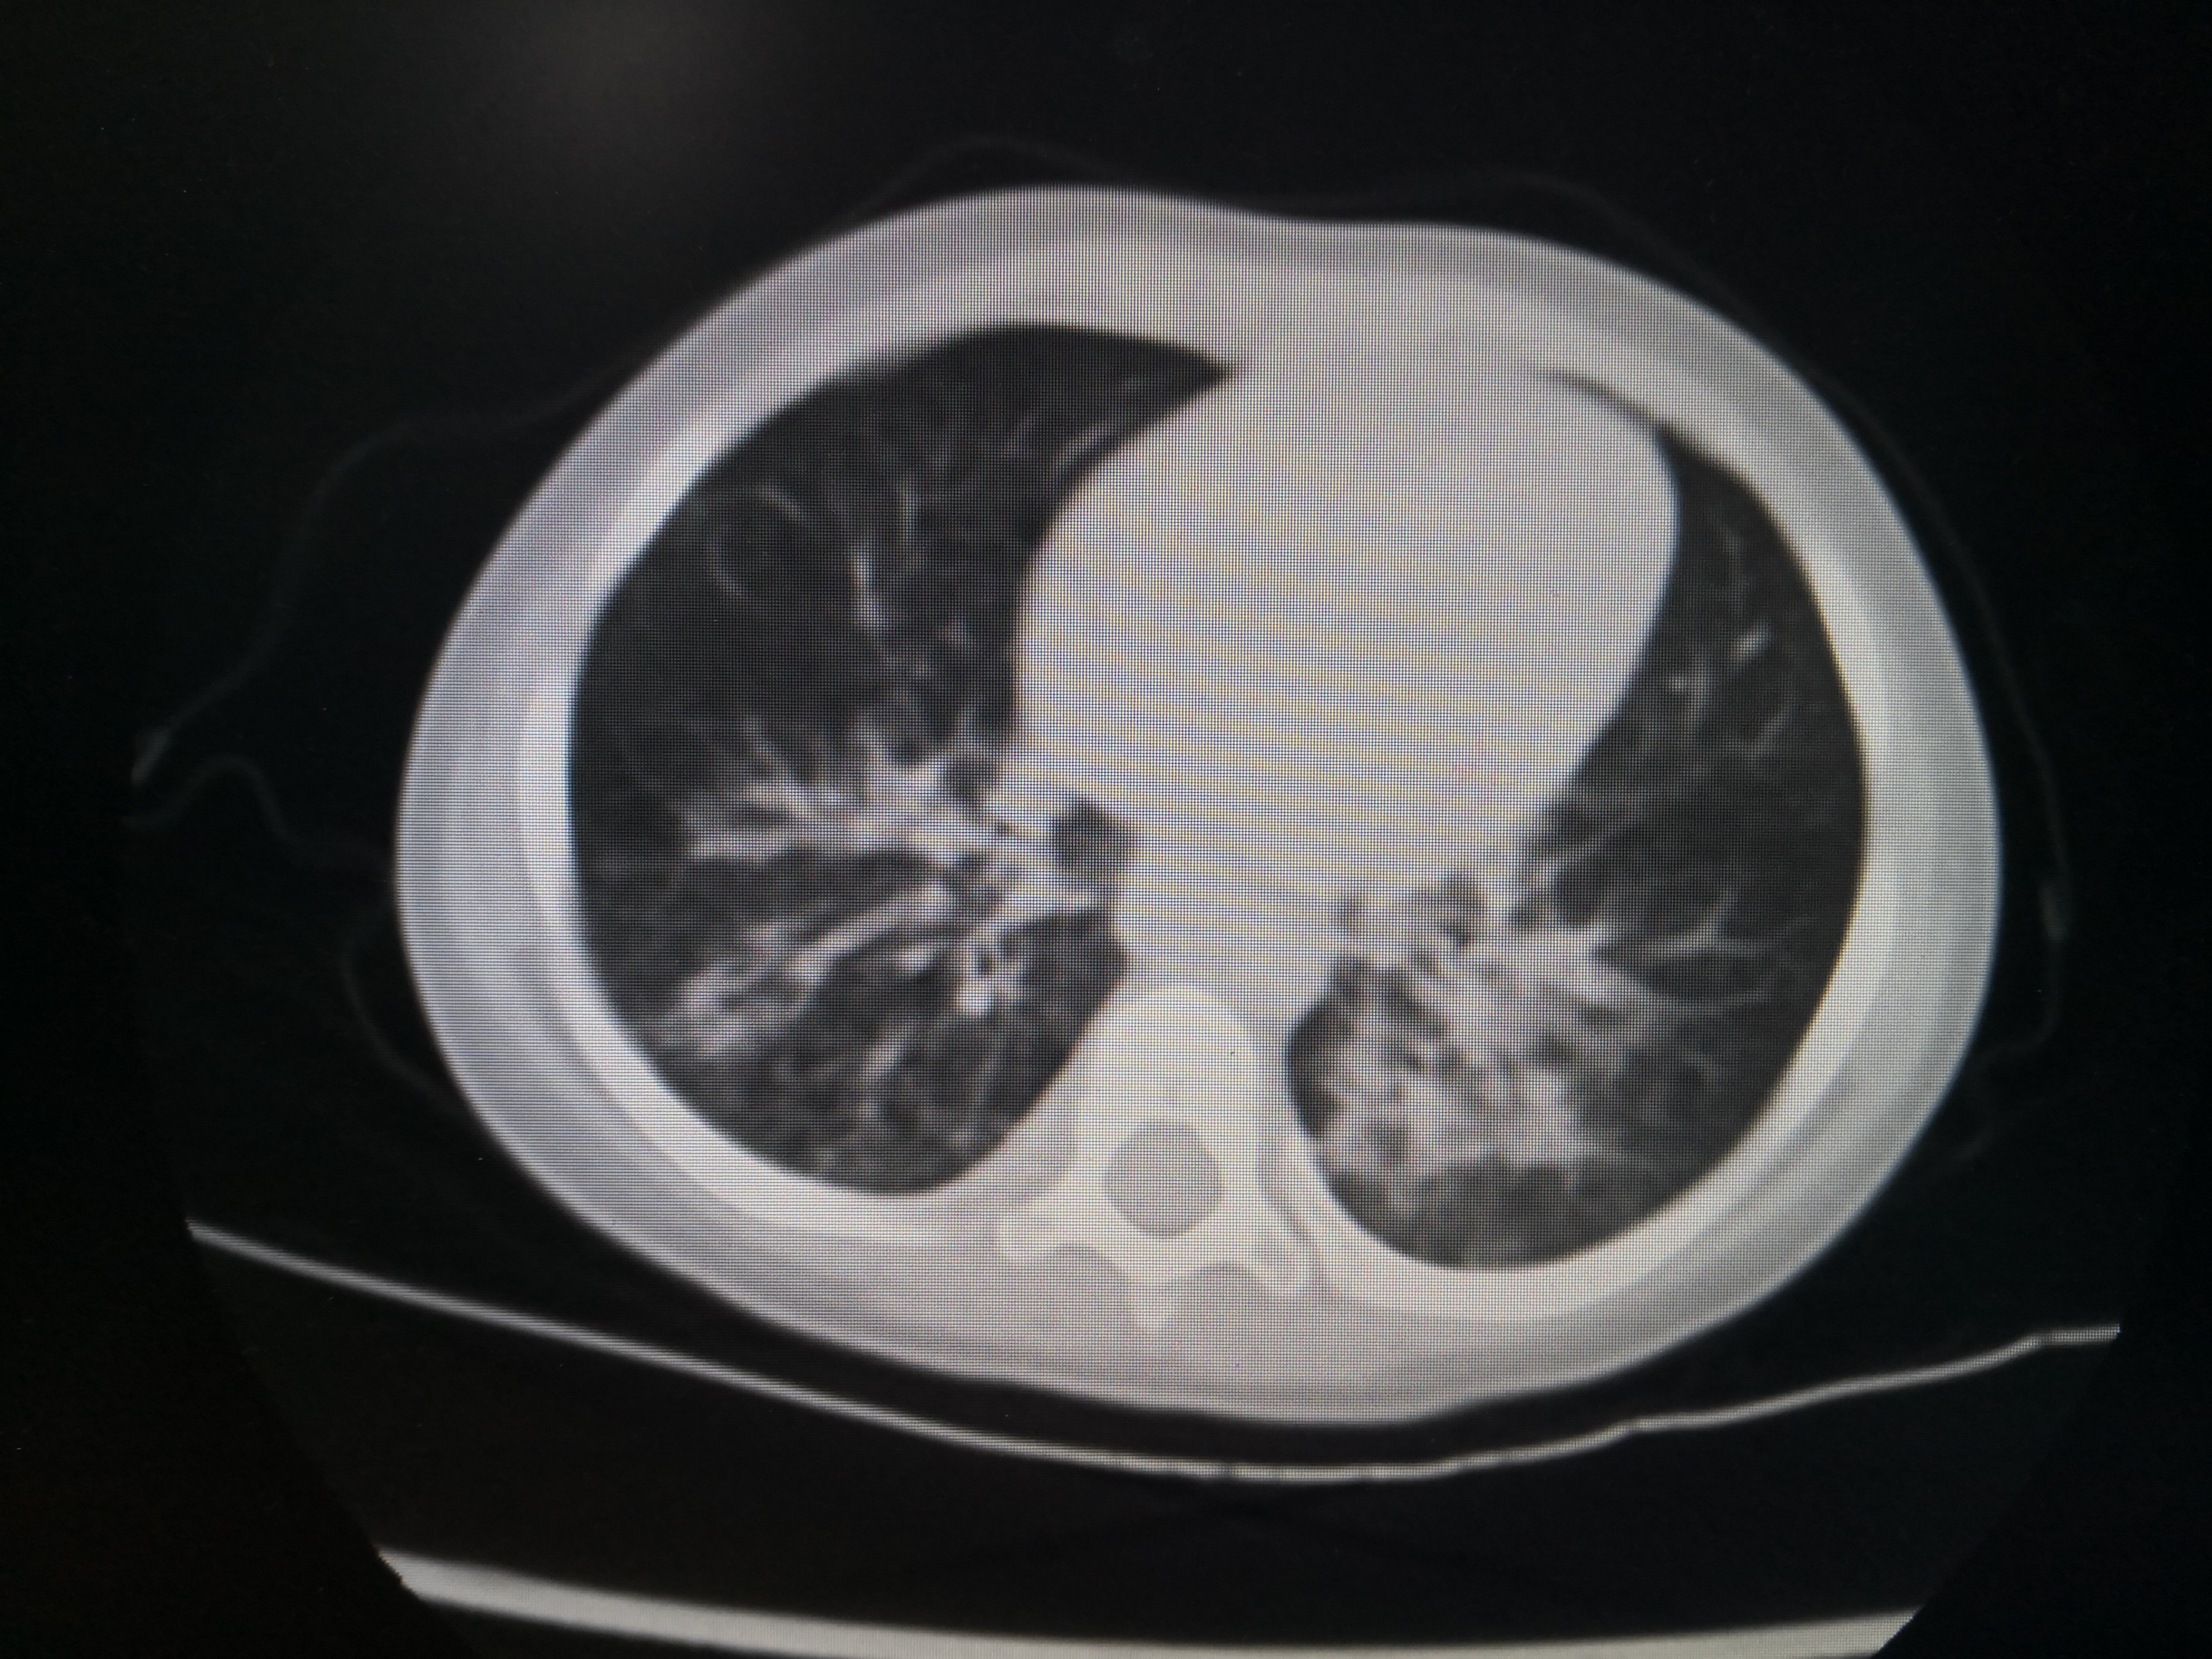

某小朋友1岁多,家住农村,在玩耍的时候不慎坠入粪池,该粪池深1.5米,不到一分钟该小朋友就已经被粪池漫过头顶仅剩一只手在外面,幸运的是旁边有大人及时发现并立即将其从粪坑里拔出。但是整个救援过程将近10分钟,小朋友被救出时已经失去意识,处于昏迷状态,急诊送至当地县医院清洗后立即120送至重庆医科大学附属儿童医院呼吸一科。入院时小朋友已经清醒,但是高烧不退,炎症指标非常高!入院后积极予以强有力的抗生素抗感染,并完善胸部CT评估双肺吸入性肺炎的严重程度,如图1

双肺炎症非常明显。CT结果出来后立即予以支气管镜灌洗治疗,在灌洗治疗过程中发现小朋友气管支气管里面大量黑色粪渣伴有较多黄色粪汁,遂将每个肺叶肺段灌洗干净,一周内完成2次支气管镜的灌洗治疗。第二次灌洗的时候双肺已经比较干净。出院后又口服了两周的强力抗生素。两周后复查胸部CT,结果如下